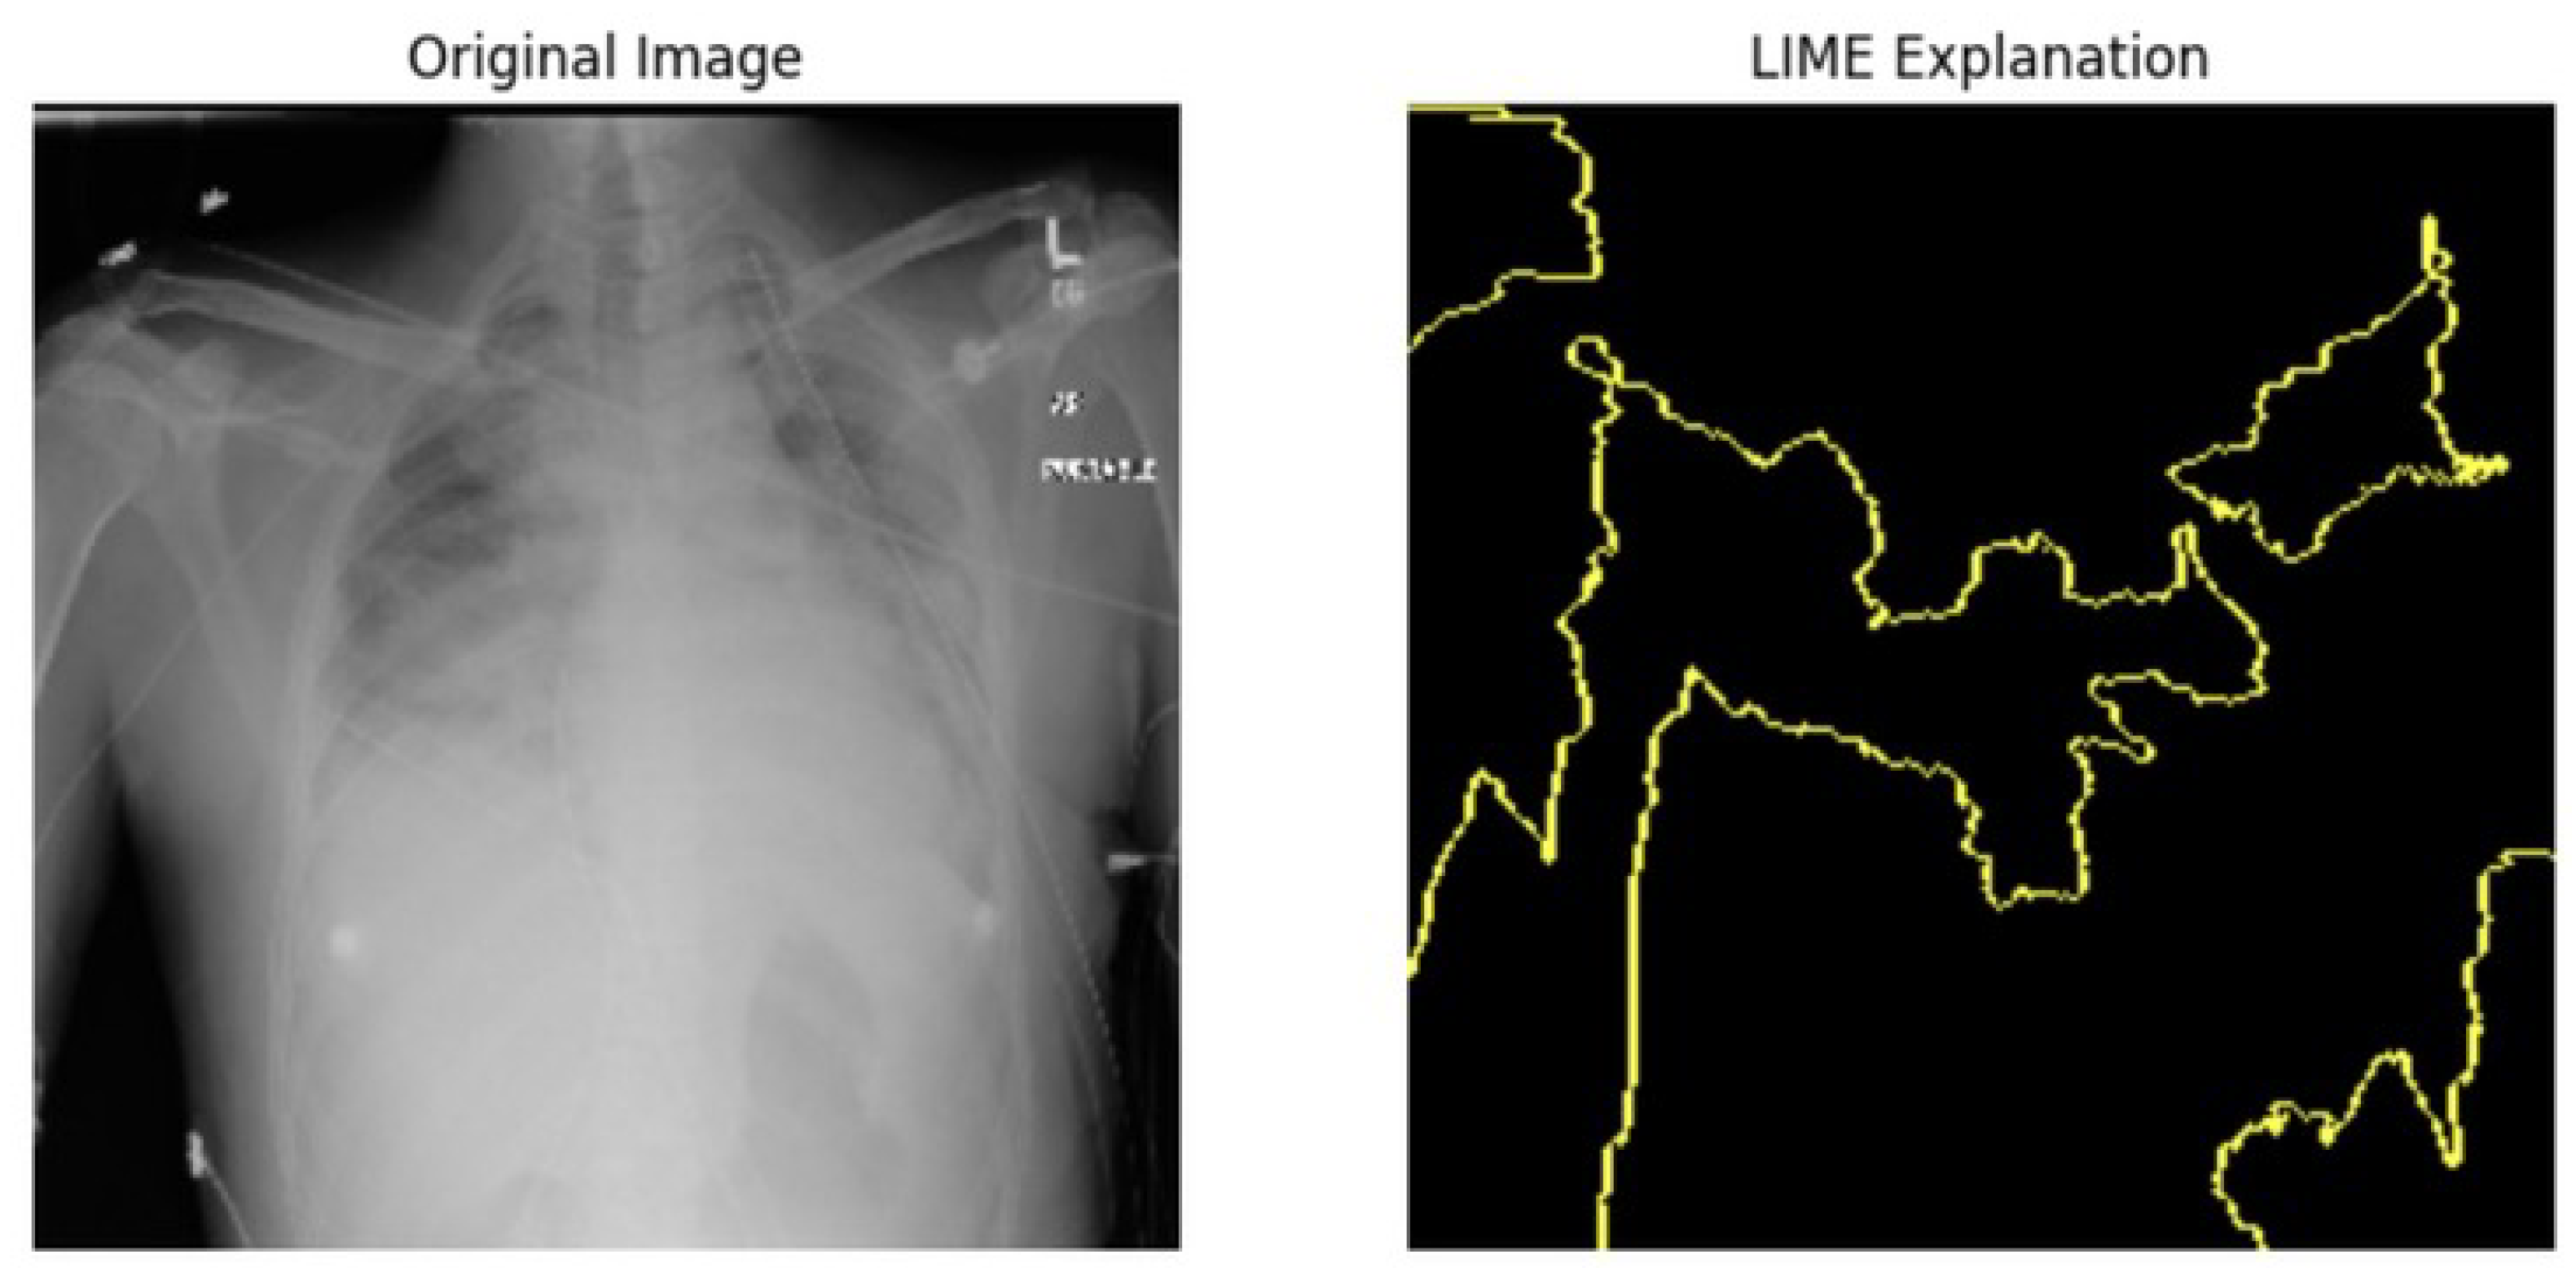

5.4.1. Local Interpretable Model-Agnostic Explanations for Clinical Validation

We applied scientific analysis on a random 7 sample, which was provided by the clinical specialist. The LIME Analysis for Image Data (a), (b), (c), (d), (e), and (f) is in Figure 22, Figure 23, Figure 24, Figure 25, Figure 26 and Figure 27. There are two parts of LIME analysis from the provided chest X-ray images to detect the disease area. Original Image and LIME explanation;

• Original Image: The patient’s thoracic cavity. It displays the typical anatomical structures of the chest, including the lungs, ribs, and heart.

• LIME Explanation: The result of applying LIME to the chest X-ray image. The yellow boundaries indicate the regions of the image that were most influential in the model’s decision-making process when determining whether the image indicated a particular condition. In this context, these regions are the parts of the X-ray that the AI model considered most important for making its diagnostic prediction.

The analysis very useful for clinicians to understand the model’s behavior and ensure that it aligns with medical expertise. The use of LIME helps in making the AI model’s interpretability decisions more transparent and interpretable. It allows medical professionals to verify whether the AI’s focus areas correspond to clinically significant regions. It also enhanced diagnostic capability of understanding which parts of the images in the AI model in refining the model further and ensures that it makes accurate and reliable predictions. This is particularly crucial in medical diagnostics where interpretability and accuracy are paramount.

Figure 25. LIME Analysis for Image Data (d) on original image to LIME explanation.